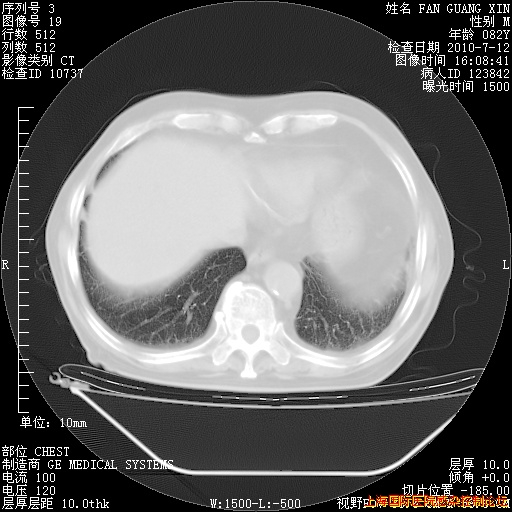

补发6月12日肺部CT肺窗

6月12日肺窗